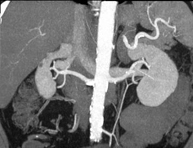

- Renal artery CT angiography

A non-invasive diagnostic test that involves studying the renal arteries by obtaining high-definition anatomical images using CT (computed tomography) equipment and iodinated contrast. With the aid of workstations specialised for arterial studies, the image quality supports 2D and 3D reconstructions. This test is recommended, for example, in patients suffering from refractory hypertension that does not respond to processing, in patients with kidney damage in order to obtain a pre-surgical ‘vascular’ map, etc.